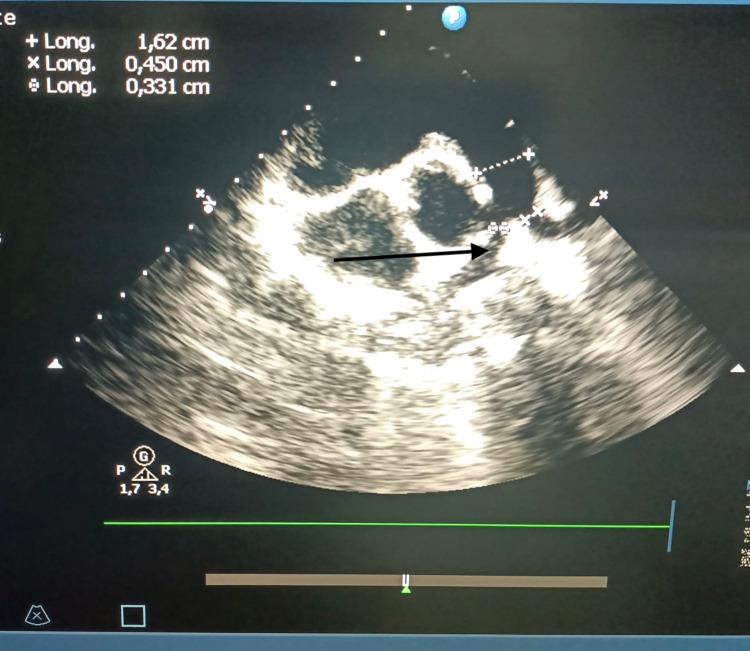

背景 法洛四联症(TOF)是最常见的青紫型先天性心脏病。TOF的手术方法不断发展,现在许多中心倾向于对TOF进行早期修复。本研究旨在确定术后并发症的发生率,如肺动脉瓣关闭不全、残余肺动脉狭窄和室间隔交通。方法 我们进行了一项横断面观察性研究,以描述性和分析性为重点,纳入了61例接受TOF手术的患者。结果 总共,39例(63.9%)患者为典型TOF,22例(36.1%)为非典型TOF。在我们的研究中,32例(56.14%)患者有肺动脉瓣关闭不全,其中20例有轻度肺动脉瓣关闭不全(占肺动脉瓣关闭不全病例的62.5%),右心室流出道扩大的患者中有79.4%有肺动脉瓣关闭不全(p<0.005)。在没有右心室流出道扩大的患者中,发现3例肺动脉瓣关闭不全,发生率为16.6%。6例(10.52%)患者有残余肺动脉狭窄。此外,本研究中发现2例(3.2%)轻度残余室间隔缺损病例。结论 TOF治疗的术后并发症很常见,患者一生都需要医疗护理。

https://cdn.ncbi.nlm.nih.gov/pmc/blobs/8148/9167490/bb34aa18182e/cureus-0014-00000024773-i04.jpg

https://cdn.ncbi.nlm.nih.gov/pmc/blobs/8148/9167490/327bd06c1e5c/cureus-0014-00000024773-i01.jpg

https://cdn.ncbi.nlm.nih.gov/pmc/blobs/8148/9167490/716c22335949/cureus-0014-00000024773-i02.jpg

https://cdn.ncbi.nlm.nih.gov/pmc/blobs/8148/9167490/7237676dcedd/cureus-0014-00000024773-i03.jpg